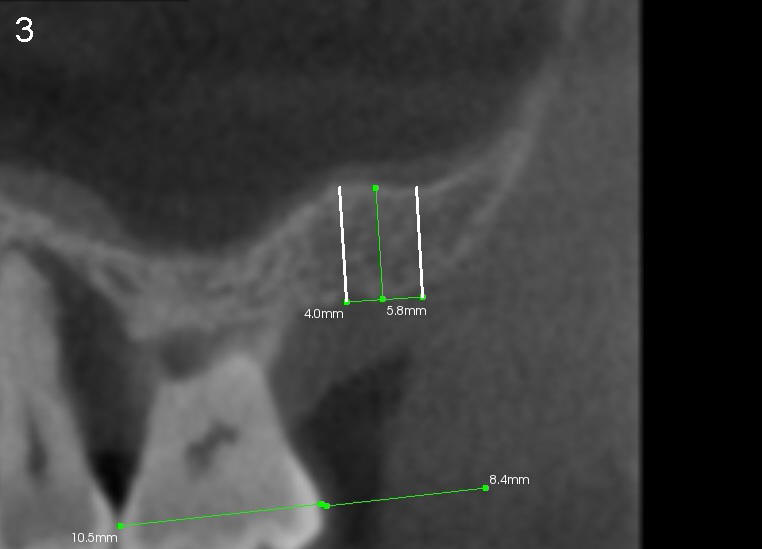

A trephine bur with outside diameter 4 mm will be used to create osteotomy and harvest the bone core (Fig.3; white lines). If the bone does not come out with the trephine bur, it will be pushed upward slowly and gently with a flat end osteotome or tap (Fig.4). When an implant is placed (Fig.5 red outline; 6x11 mm), it is covered by the vital bone above with blood supply coming from the sinus membrane.